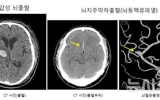

건강 뉴시스2025. 09.11[나이스데이] 아침, 저녁으로 온도차가 많이 벌어지는 '환절기'가 찾아왔다. 일교차가 커지는 환절기에는 뇌혈관이 좁아지고 혈압도 상승해 뇌졸중 발생 확률이 높아져 주의가 요구된다. 극심한 두통과 마비증상이 나타나는 뇌졸중은 국내 사망 원인 4위이자, 전 세계적으로 10초에 한 명씩 뇌졸중으로 사망한다는 통계가 있을 정도로 위험한 질환이다. 11일 의료계에 따르면 흔히 '중풍'으로 알려진 뇌졸중은 갑자기 뇌혈관에 문제가 생기는 병이다. 뇌졸중은 뇌에 혈액을 공급하는 혈관이 막혀 발생하는 허혈성(뇌경색) 과 뇌로 가는 혈관이 터…

건강 뉴시스2025. 09.11[나이스데이] 청년 고용률이 16개월 연속 전년보다 감소하면서 2009년 글로벌 금융위기 이후 최장기간 하락세를 기록했다. 청년 고용률 감소 흐름은 코로나19 때보다 이미 더 장기화됐다. 정부는 경기 부진의 흐름 속에서 기업의 경력직 선호, 청년의 지방 기피·워라벨 선호 등이 복합적으로 작용하고 있다고 진단했다. 전체 고용률은 60세 이상 취업자가 늘어나면서 역대 최고치를 기록했지만 청년층의 취업지표는 악화를 지속하는 양상이다. 11일 통계청이 전날 발표한 '2025년 8월 고용동향'에 따르면 15~29세 청년 고용률…